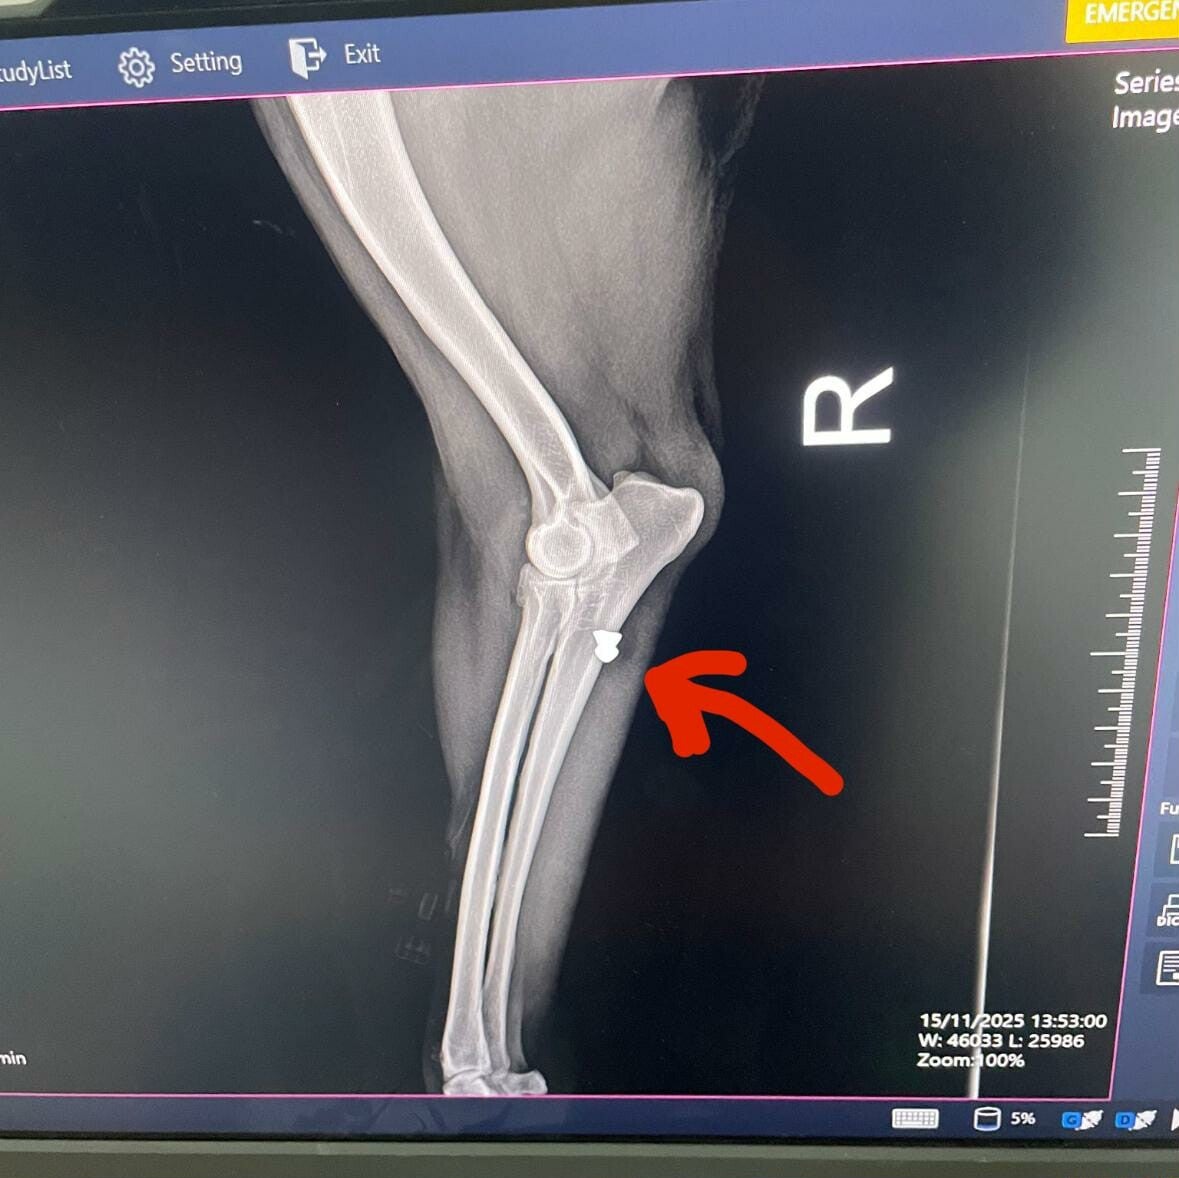

La petite mamie Poupette… une survivante au cœur immense. Elle a passé sa vie dans la rue, partageant un grand terrain avec d’autres chiens, formant avec eux une sorte de petite famille de fortune. Parfois, timidement, elle s’approchait des humains pour demander un peu d’eau, un peu de nourriture… juste assez pour tenir un jour de plus. Puis un jour, quelqu'un s'est amusé à lui tirer dessus avec un fusil. Elle a une balle plantée dans sa patte arrière.